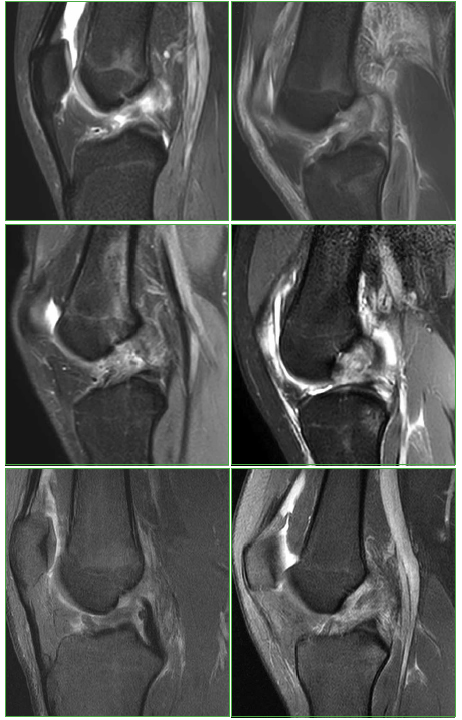

Figura 9.

Resonancia magnética de rodilla. Imágenes de lesión del ligamento cruzado anterior en distintos atletas.

Algunos artículos mencionan que el 80% de las lesiones afecta a los tejidos blandos (tendones, músculos, ligamentos) y que el 20% restante incluye fracturas y lesiones de órganos internos.5 En relación con el tipo de lesión, Osorio y cols. mencionan que, en los JJ.OO. de 1968 y 1974, las lesiones tratadas más frecuentes fueron: esguinces, desgarros y contusiones.5 En nuestra casuística, las lesiones más frecuentes fueron las de tejidos blandos en 16 casos (48,48%), seguidas de las lesiones óseas en 12 atletas (33,33%), con un neto predominio de los miembros inferiores (26 casos) contra seis en los miembros superiores (relación 4,3:1). Las lesiones informadas más frecuentes fueron: desgarro del ligamento cruzado anterior, ya sea aislado o asociado a desgarro meniscal (9 casos, 27,27%), seguido de fractura, edema óseo con desgarro de ligamentos del tobillo o sin él (8 casos, 24,24%) y fractura de huesos de la muñeca con lesiones ligamentarias asociadas o sin ellas (5 casos, 15,15%).